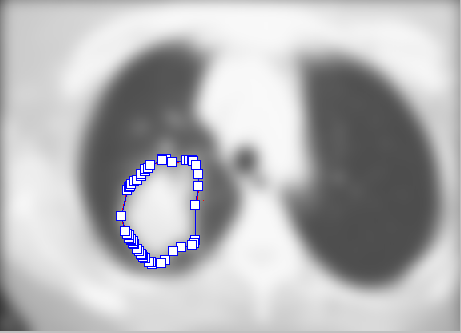

Однією з нагальних медичних та соціальних проблем сучасності є боротьба з онкологічними захворюваннями. Підвищення ефективності та якості лікування в онкології, постійне оновлення терапевтичних методик є завжди на часі. Одним з найбільш поширених методів лікування онкохворих є променева терапія, суть якої полягає в дії на пухлину іонізуючим випромінюванням. Але при опроміненні вражаються не лише новоутворення, а й навколишні здорові тканини, тому важливо точно сформувати поле опромінення та забезпечити найбільш ефективний вплив на опромінюваний об’єм. Нині для цього використовують багатоелементні коліматори за технологію Intensity-Modulated Radiation Therapy (IMRT). Для налаштування коліматора необхідно задати точний контур мішені. Отже, визначення істинної конфігурації новоутворення за діагностичним зображенням є однією з основних проблем планування променевої терапії. В роботі здійснений пошук методик обробки томографічних зображень з метою розпізнавання контуру пухлини в легенях (рис.1а).

Рисунок 1 – Етапи формування контуру мішені

Вхідними даними обрано результати рентгенівської або магніторезонансної томографії, котрі найбільш придатні для розрахунку поля опромінення, а саме: мають високу інформативність та точність позиціонування пацієнта. Зменшення суб’єктивного впливу лікаря при визначенні об’єму мішені мало б уточнити отримані результати, особливо про роботі з тривимірними структурами. Основними етапами обробки зображення були: застосування фільтра Гауса (б), порогова обробка (в), отримання зображення з накладеним контуром, котрий отримано після обробки двоколірного зображення фільтром Лапласа (г). Далі отримані зі зрізів контури новоутворень використовують для побудови об’єму методом воксельної реконструкції. Після цього проводиться уточнений розрахунок індивідуального поля опромінення.